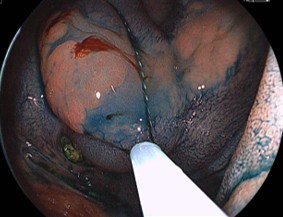

粘膜下層に局注して、挙上がえられれば内視鏡的粘膜切除術(EMR)の適応となります。

スネアリングするための、適切な場を設定されました。あとはスネアリングするだけです。